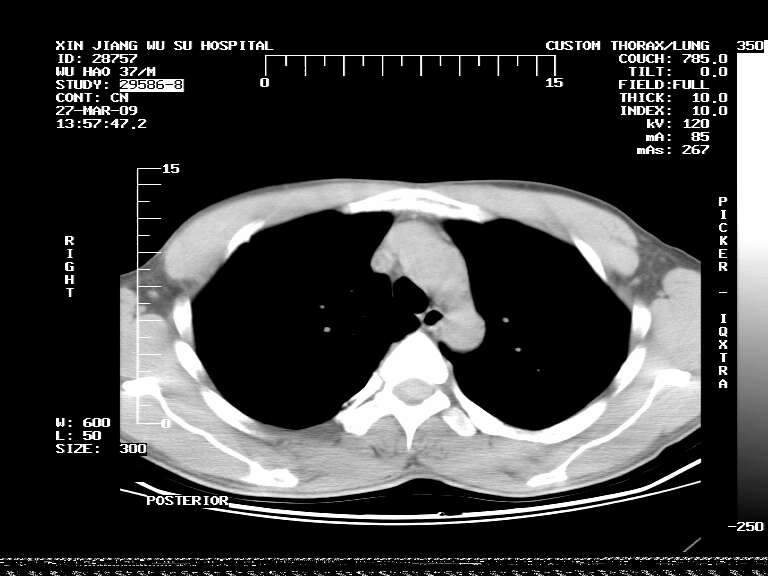

男,37岁,体检胸透发现阴影。

患者体检发现 无症状 左肺下叶占位,边缘模糊,可见血管聚束、分叶、胸膜牵拉,增强呈不均匀性强化。 首先考虑左肺下叶周围型肺癌,建议穿刺活检。

左肺下叶见一结节病变,边缘欠清不光滑,与胸膜粘连且胸膜局限性增厚,注药后呈环形强化,动脉期壁呈明显点环状强化,静脉期壁强化减低,中心密度低无强化,灶周无明显的卫星灶和水肿区(晕征)---考虑周围性肺癌,不除外感染性病变,建议穿刺活检。

左肺下叶软组织病灶,密度较高,内见点状钙化,其周围见子灶,邻近胸膜扁平样增厚.c+病灶强化明显,中心强化弱.诊断:左肺下叶结核瘤.

左肺下叶大片实变影,内靠胸膜见不规则更高密度结节灶,边缘强化,相邻胸膜增厚,胸膜下脂肪线存在。考虑炎症,结核可能。